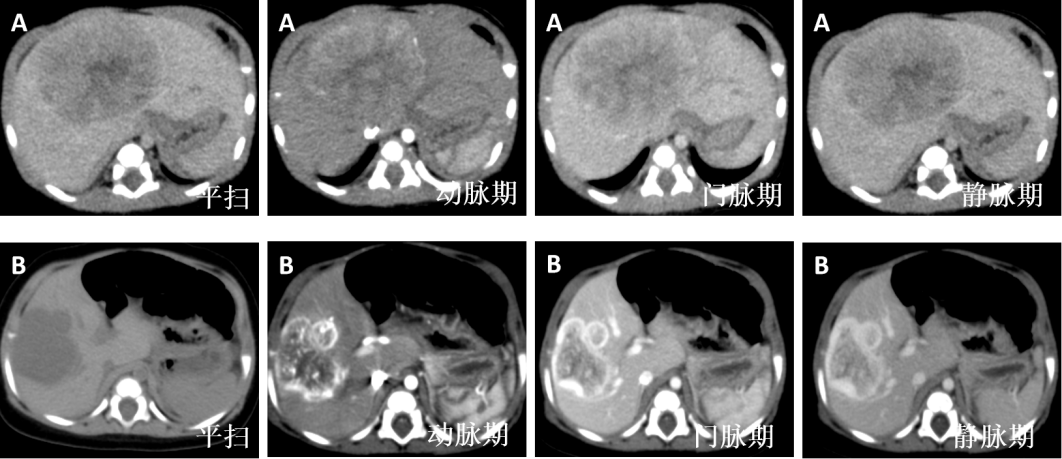

帮助诊断医生区分肿瘤类型(如肝母细胞瘤vs肝婴儿型血管瘤)。

CT增强扫描应用于病变性质鉴别

A.CT平扫+增强扫描检查后诊断为:肝母细胞瘤

B.CT平扫+增强扫描检查后诊断为:肝婴儿型血管瘤